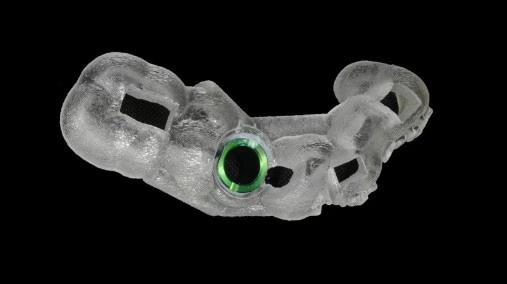

Máng hướng dẫn phẫu thuật cá nhân hóa: dụng cụ được làm riêng cho từng bệnh nhân để hỗ trợ bác sĩ đặt trụ Implant đúng vị trí. Khi phẫu thuật, bác sĩ chỉ cần khoan qua các lỗ định hướng trên máng

![]() |

| Máng hướng dẫn phẫu thuật cá nhân hóa |